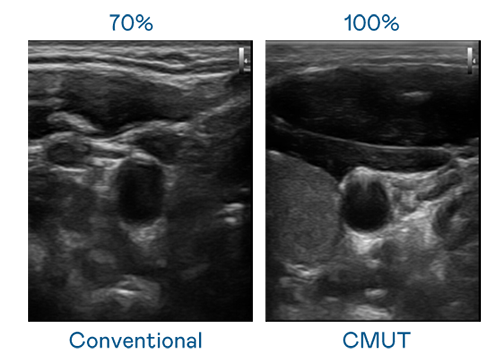

CMUT 技术是一种用电容式微机电元件来产生超音波讯号的技术。与传统 PZT 压电式技术相比,CMUT 频宽增加 30%,更宽频的超音波讯号让影像解析度大幅提升,是实现高影像品质医疗超音波扫描、促进精准医疗发展的关键技术。

大频宽带来超清晰影像

超音波影像的解析度高低,首先取决于探头能发出的讯号频宽。w66旗舰厅 CMUT 可提供高清晰的超音波讯号,提供高频宽、高灵敏度、影像纹理细节更高的超音波影像,协助医护人员缩短影像判读时间及利用精准的医疗影像进行诊断。